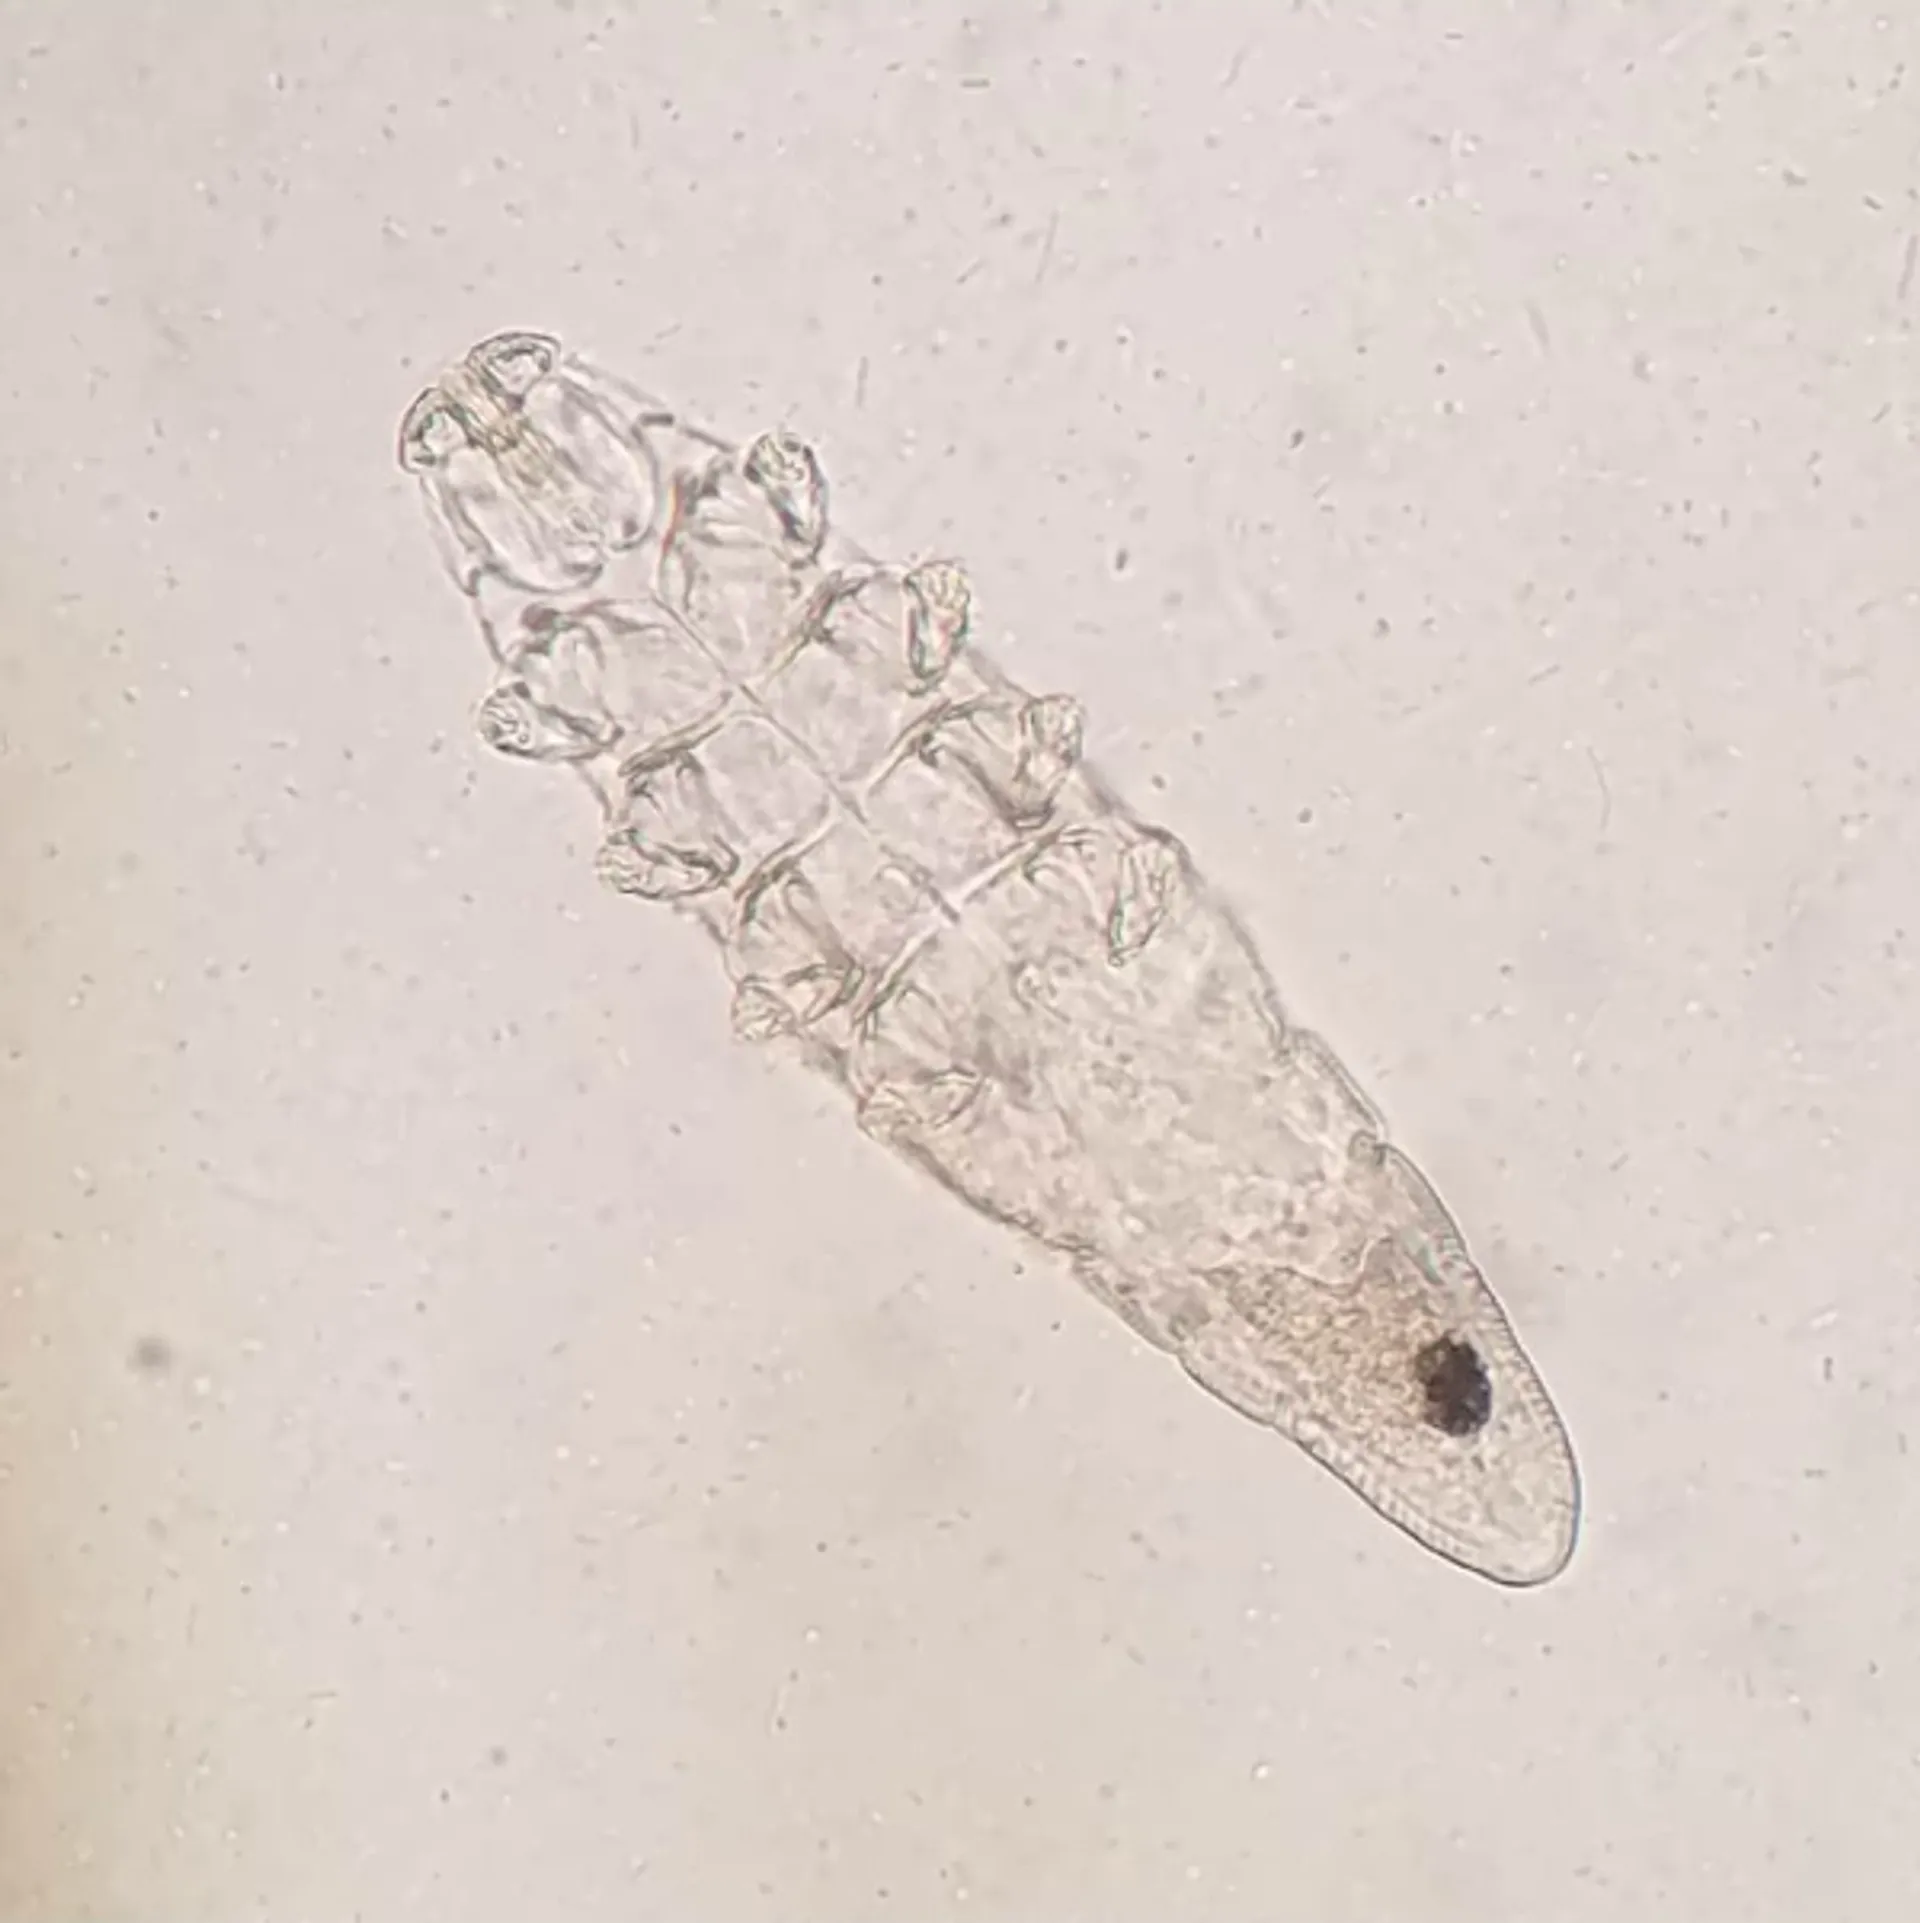

Ve Demodex có hình dạng thon dài, giống như một điếu xì gà với tám chân ngắn ở phần đầu giúp chúng đào sâu và di chuyển linh hoạt trong các nang lông.